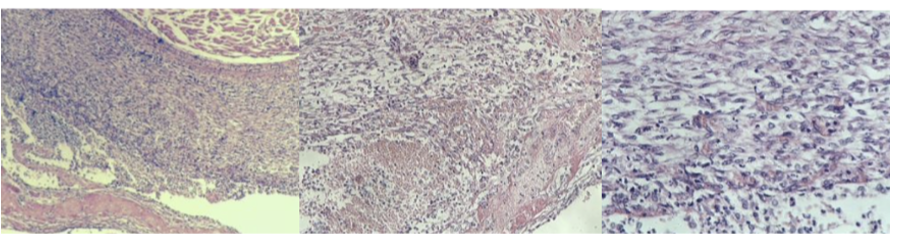

Glomerulonephritis chronica

Bilde 1: hyaline in glomeruli and tubules

bilde 2: periglomerulitis chronica, gradual fibrotization of glomeruli

bilde 3: higher magn. of bilde 1, glomeruli with neutrophils and hyaline